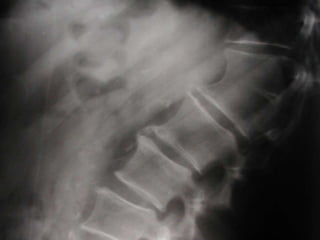

LUMBAR LATERAL

Estructuras Visualizadas

•Cuerpos Vertebrales T12-S1

•Espacios discales T12-L5

•FIV's

•PE's

•Facetas Articulares

•Pediculos

•Aorta Abdominal (cuando hay

ateroesclerosis)